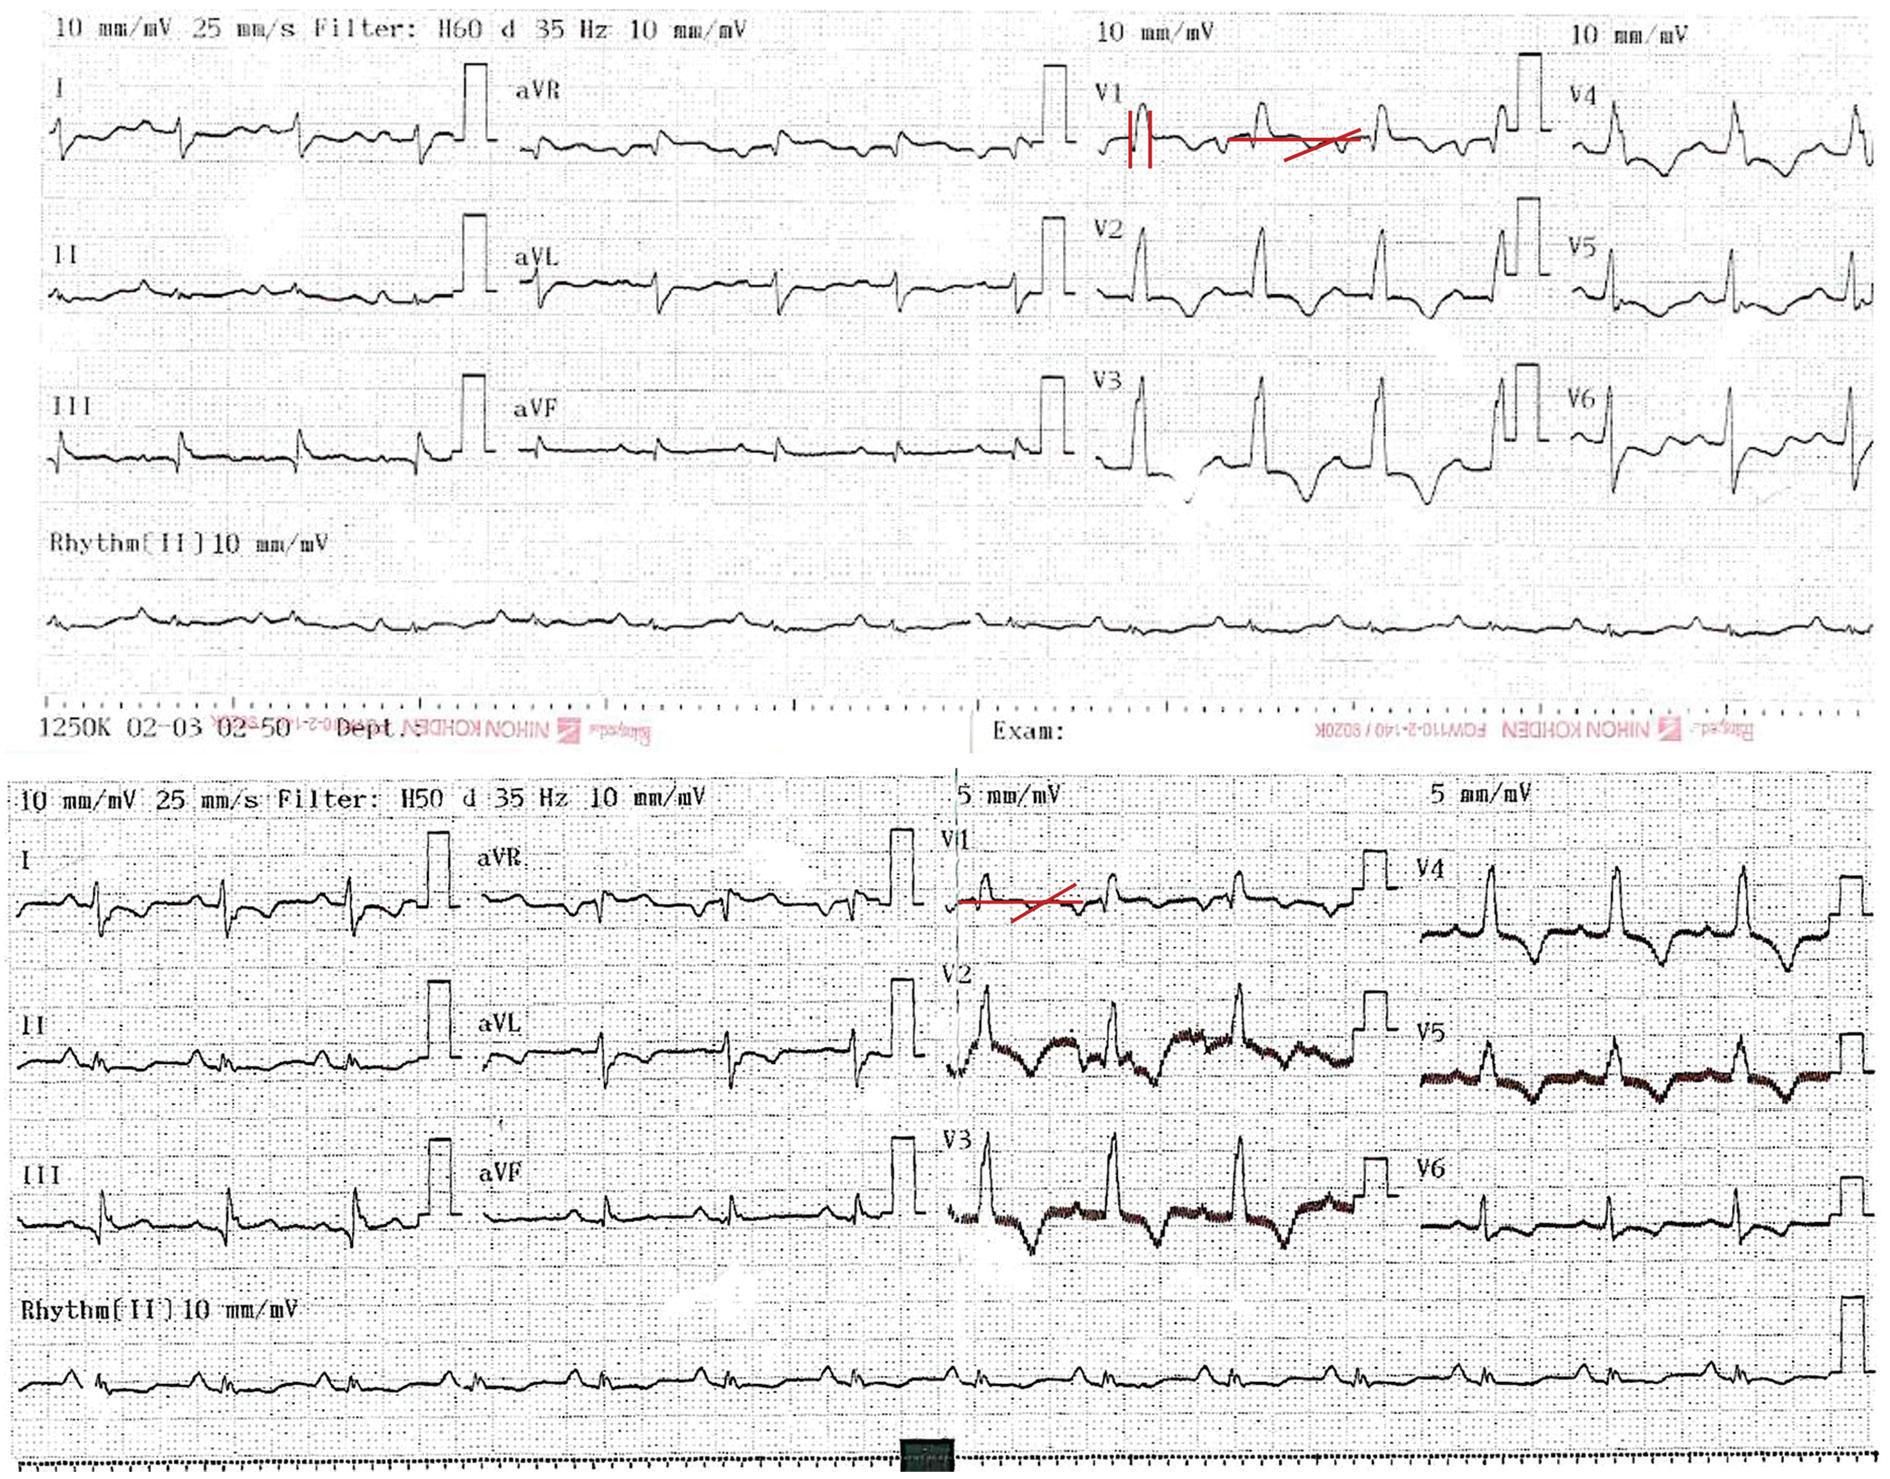

A 31-year-old male started 1 day before admission with pain in the upper right limb, dizziness, nausea, diaphoresis, and paleness followed by loss of postural tone and loss of consciousness 3 min long. He denied previous similar episodes, fever, diarrhea, chest pain, or head trauma. The patient's vital signs, neurological and cardiovascular examinations on admission were normal. The patient history was notable for HT because of dilated cardiomyopathy 6 years before the current even. Immunosuppressive therapies at the time of presentation included cyclosporine, mycophenolate, and prednisolone without recent changes. The patient denied taking herbal supplements. A differential cell count, leukocytes, hemoglobin, blood glucose, and electrolyte levels were normal, with cyclosporine levels in subtherapeutic range (122.8 ng/mL). An electrocardiogram (ECG) showed sinus rhythm, with a pattern of right bundle branch block, with a QT interval of 420 ms and a QTc interval by Bazzet's formula of 530 ms. R-R distance was 0.64 s (Fig. 1A) that had not been documented on his follow-up ECG in the outpatient heart transplant consultation. His transthoracic echocardiogram (TTE) documented severe left ventricular dysfunction (left ventricle ejection fraction [LVEF]: 20%), with generalized hypokinesia, right ventricle of normal size but with systolic dysfunction (tricuspid annular plane systolic excursion [TAPSE] 10 mm and peak systolic velocity of tricuspid annulus color tissue Doppler 4 cm/s) and global longitudinal strain (GLS) was −5.5%. The right heart catheterization document increased pressures (central venous pressure 18 mmHg, wedge 27 mmHg, and mean pulmonary arterial pressure of 30 mmHg) and coronary angiography without vasculopathy. Endomyocardial biopsy (EMB) (Fig. 2) revealed acute humoral and cellular rejection (Grade 3R ISHLT). The specific donor antibody was positive against HLA Class II DRB *1.

Figure 1 A: electrocardiogram on admission to the emergency: sinus rhythm, QRS of 100 ms with the right bundle branch block morphology. QRS axis slightly deviated to the left. QTc interval by Bazett's formula 530 ms and QT interval of 420 ms. Heart rate: 96 bpm, R-R distance: 0.64 s. B: electrocardiogram after anti-rejection management: QTc of 424 mseg by Bazett's formula and QT interval of 360 mseg, Heart rate: 83 bpm. R-R distance: 0.72 seg.

With these findings consistent with an acute rejection of the graft, steroid bolus was initiated as well as consolidation therapy with plasmapheresis for 2 weeks followed by immunoglobulin and subsequent rituximab. The electrocardiographic changes were corrected after completion of plasmapheresis and immunoglobulin management (Fig. 1B; QTc of 424 mseg by Bazett's formula and QT interval of 360 mseg, heart rate: 83 bpm), with resolution of symptoms. His TTE showed a LVEF 55% without segmental contractility disorders, with recovery of the right ventricular function (TAPSE 21 mm, S´-wave velocity 10 cm/s) and GLS of −6.6%. The control EMB showed focal lymphocytic and 30% CD4 positivity in capillaries (Grade 1R ISHLT), concluding improvement with the management to a mild rejection. He was discharged home with an immunosuppression management adjustment as the cause of rejection was considered to be related to subtherapeutic levels of cyclosporine.